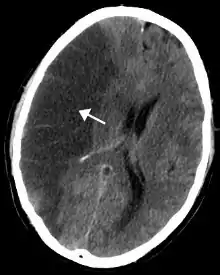

Risques de cancer

.jpg.webp)

La consommation de tabac est la première cause de cancer connue dans le monde. Elle est impliquée dans 33,9 % des cancers mondiaux[40].